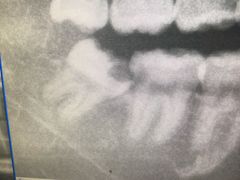

• 上海市杨浦区牙病防治所

• -上海市杨浦区牙病防治所